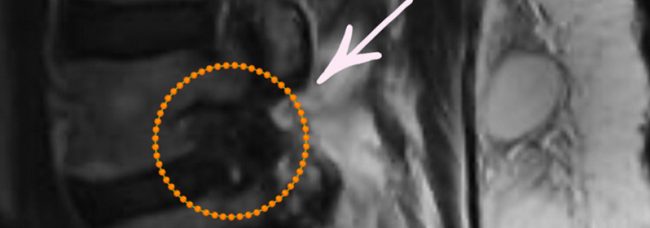

O cisto facetário na coluna lombar é uma pequena bolsa que contem líquido articular e se forma decorrente de alterações degenerativas da articulação facetária da coluna. O problema é quando surge dentro do canal vertebral onde estão os nervos da coluna. Trata-se de uma condição benigna, mas quando comprime o nervo da coluna costuma causar dor importante…